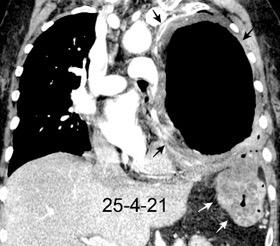

Tromboembolismo pulmonar.

Frecuencia del derrame:

Rx: 32%. TC: 47%

Unilateral. 85%

< 1/3 del hemitórax: 90%

Todos exudados

58% con eritrocitos

21% tabicación lo que causa demora en el diagnóstico

TEP. Empiema pleural. Atelectasia redonda

Porcel JM et al. Analysis of pleural effusions in acute pulmonary embolism: radiological and pleural fluid data from 230 patients. Respirology 2007/ Iguchi T et al. Desquamation of the subpleural lung parenchyma caused by empyema after pulmonary embolism: A case report. Respirol Case Rep. 2022 .